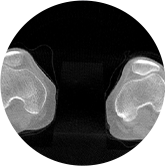

髋关节

膝关节

精准诊断

手术方案规划

术后随访